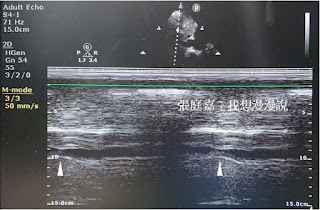

從subcostal view (longitudinal axis)去看IVC,可見它進入RA,一般測量ICV的直徑昰距離RA交接處二公分。

| 距離RA入口二公分處 |

| 開啟M-mode可以觀察動態變化 |

自發呼吸時的直徑與CVP相關 (參考心臟超音波:IVC看甚麼?之一);

使用呼吸器的病人IVC隨著呼吸改變其直徑12-18%被視為與fluid responsiveness相關。[5-6]